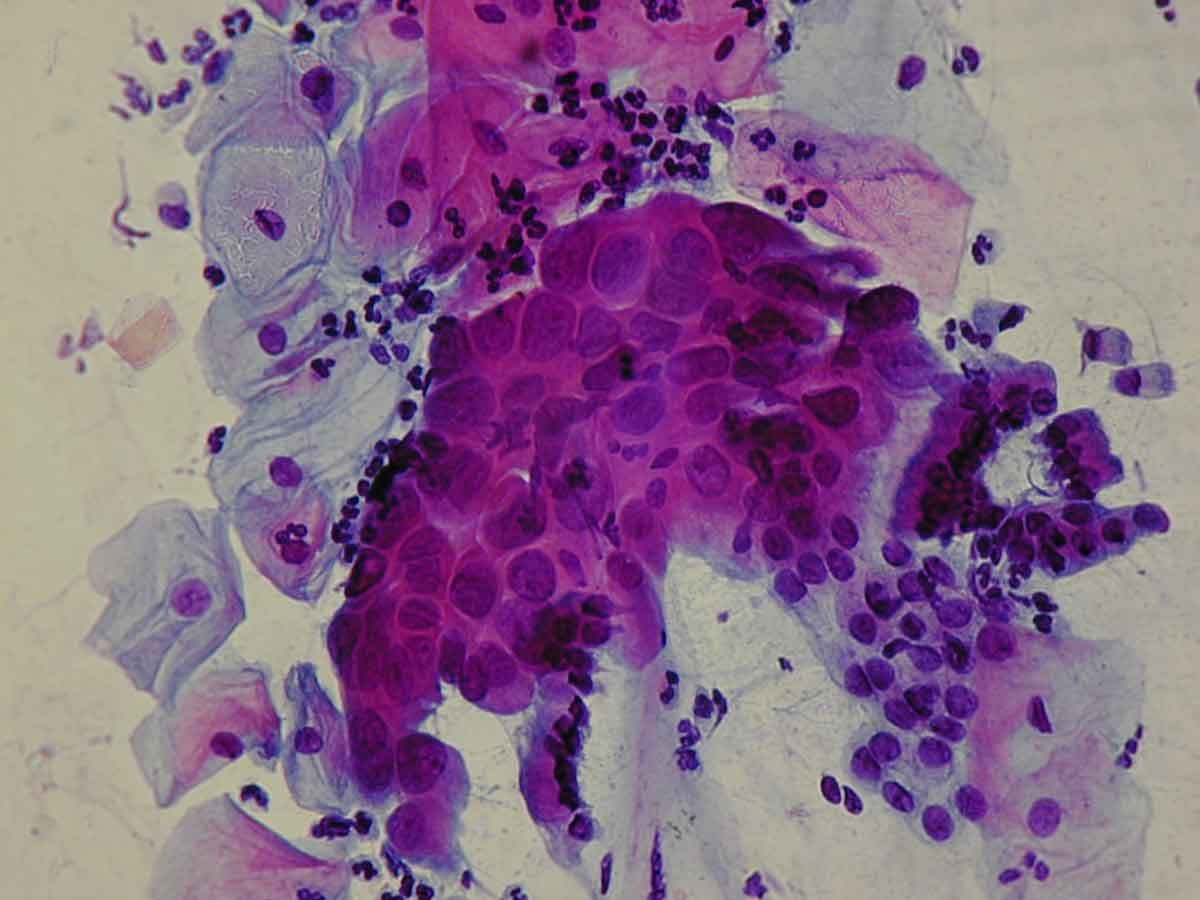

Citología diagnóstica

BIOPSIA Y CITOLOGÍA GINECOLÓGICA

CITOLOGÍA